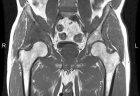

D.R. - 65 year old male, c/o worsening right hip/buttock pain for six months. Pain is constant, worse with activity. Tylenol helps a bit. No F/C or constitutional sx.

PMH: Crohn's disease, nephrolithiasis, prostate infection, gallstones